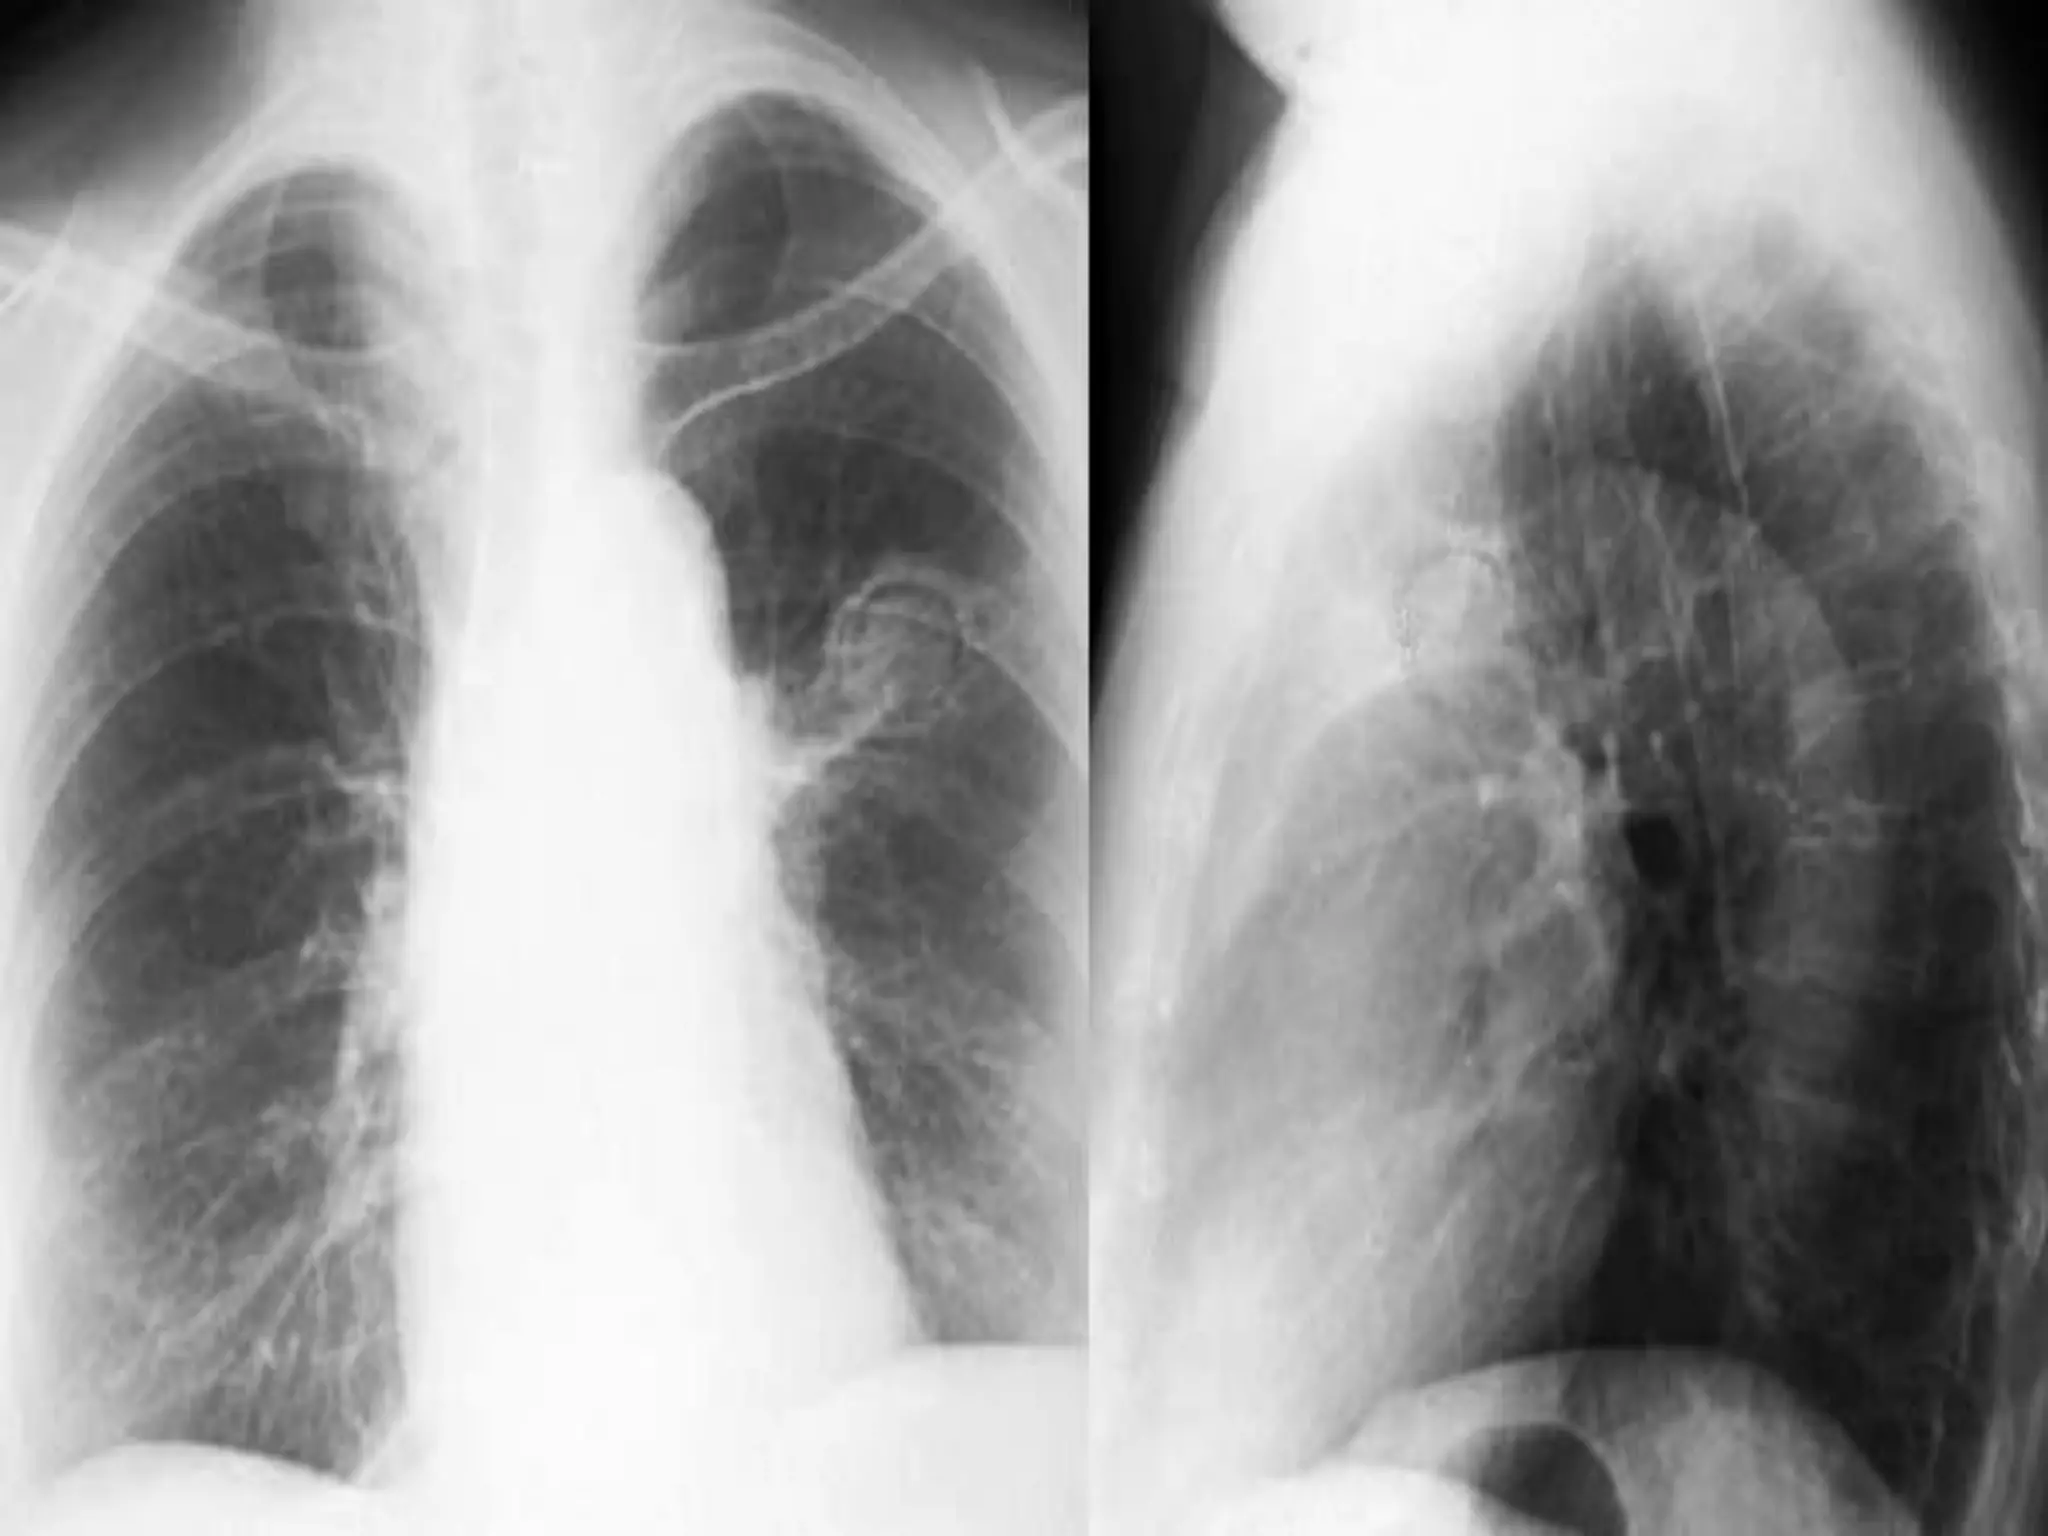

Atelectasis Left Upper

Lobe

Hazy density over left

upper lung field

Loss of left heart

silhouette

Tracheal shift to left

Lateral

A: Forward movement of

oblique fissure

B: Herniated right lung

C: Atelectatic LUL